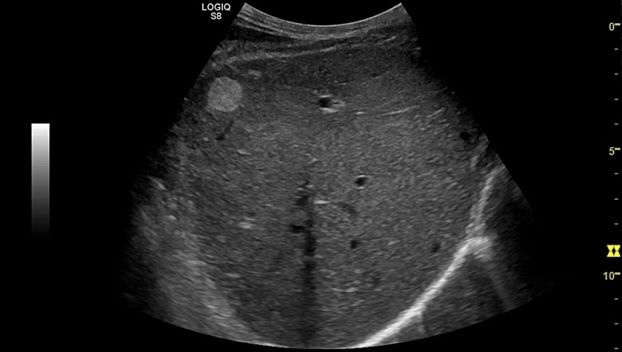

Клинические изображения

Logiq S7 XDclear — УЗИ аппарат нового поколения, который обеспечивает простой и комфортный рабочий процесс, высокую производительность и предлагает широкий набор современных инструментов для проведения уверенной диагностики. Его расширенный функционал включает такие возможности как B-Flow — недопплеровская технология отображения кровотока в B-режиме, компрессионная эластография (качественная и полуколичественная), количественный анализ васкуляризации, функцию В-Steer+ — изменение угла наклона УЗ луча в B-режиме, 3D/4D диагностику и мультимодальную визуализацию.

- Абдоминальные исследования

Система LOGIQ S7 проектировалась для использования по широкому спектру клинических приложений, но, чтобы ещё больше расширить ее функциональность и повысить уровень производительности, инженеры компании GE добавили технологию XDclear и обновили конструктив модели.

LOGIQ S7 XDclear — УЗИ аппарат нового поколения, который обеспечивает простой и комфортный рабочий процесс, высокую производительность и предлагает широкий набор современных инструментов для проведения уверенной диагностики.

Ультразвуковой аппарат LOGIQ S7 XDclear предназначен для использования специалистами из различных областей диагностики. Его расширенный функционал включает такие возможности как B-Flow — недопплеровская технология отображения кровотока в B-режиме, компрессионная эластография (качественная и полуколичественная), количественный анализ васкуляризации, функцию В-Steer+ — изменение угла наклона УЗ луча в B-режиме, 3D/4D диагностику и мультимодальную визуализацию.